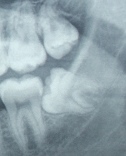

Terceiros molares – dentes do siso

terceiros molares sisoNo final da adolescência, os terceiros molares erupcionam e os dentes inferiores da frente gradualmente ficam mais irregulares.

No passado, pensava-se que a pressão exercida pelos terceiros molares causava aumento da irregularidade. Contudo, estudos recentes sugerem que estes dois eventos não estão relacionados.

De facto, é normal que os incisivos inferiores fiquem mais apinhados com o crescimento, quer estejam ou não presentes os terceiros molares!!!

Hoje em dia, os terceiros molares não são extraídos por rotina. Um raio-x é essencial para uma avaliação de cada caso em particular.